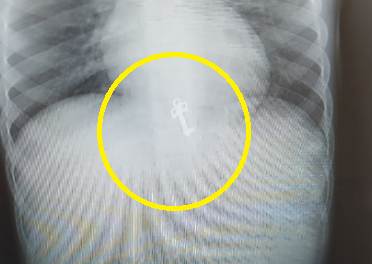

הבת הגדולה של המשפחה חיפשה את המפתח הדוקרני של היומן שלה, לאחר שהמשפחה חשדה, כי האח בן השבע בלע את זה, הם התפנו ליומן, שם נמצא המפתח בתוך קיבת האח (חדשות בריאות)